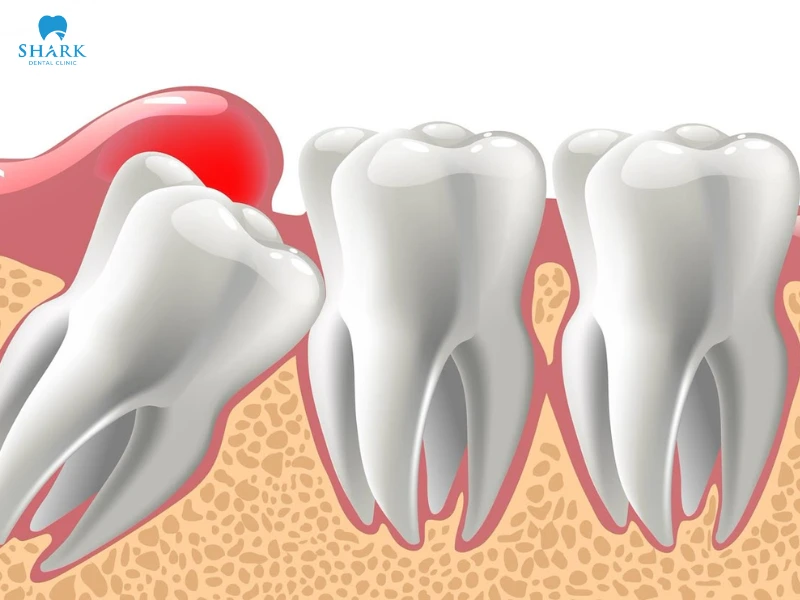

Lợi trùm răng khôn thực chất là quá trình khi răng khôn mọc lên xuất hiện dấu hiệu sưng tấy, có phần lợi bao trùm che phủ hết bề mặt của răng. Khi răng mọc sẽ đâm lên phần lợi, gây hiện tượng sưng viêm, đau nhức, ảnh hưởng đến quá trình ăn nhai.

Chưa kể một số trường hợp răng khôn bị lợi trùm còn gây đau nhức khó chịu kéo dài, dẫn đến ảnh hưởng đến sức khỏe và quá trình chăm sóc răng miệng. Đây là một trong những bệnh lý gây hoang mang, ám ảnh đối với nhiều người.

Vì răng khôn mọc ở vị trí cuối trên cung hàm, không đủ chỗ để chen lấn khi các răng kế cận đã mọc hoàn thiện. Do đó, răng mọc sẽ bị mấp mé phần lợi, cọ sát với nướu và dẫn đến hiện tượng răng khôn bị lợi trùm.

Răng khôn mọc lệch

Một số những trường hợp lợi trùm răng khôn là do răng không thể mọc đúng hướng. Răng khôn mọc lệch, đâm vào răng số 7 hoặc răng khôn mọc ngầm.

Từ đó phần lợi sẽ sưng tấy, đau nhức do vi khuẩn dễ dàng tích tụ. Lợi sẽ có dấu hiệu nhiễm trùng và xuất hiện tình trạng lợi trùm lên răng khôn.